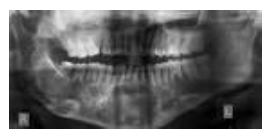

Radiographic appearance :

Medullary portions of bone are rarefied and present irregular trabeculations. Radiographically the condition presents as a unilocular, multilocular or ground-glass or peau de orange appearance.